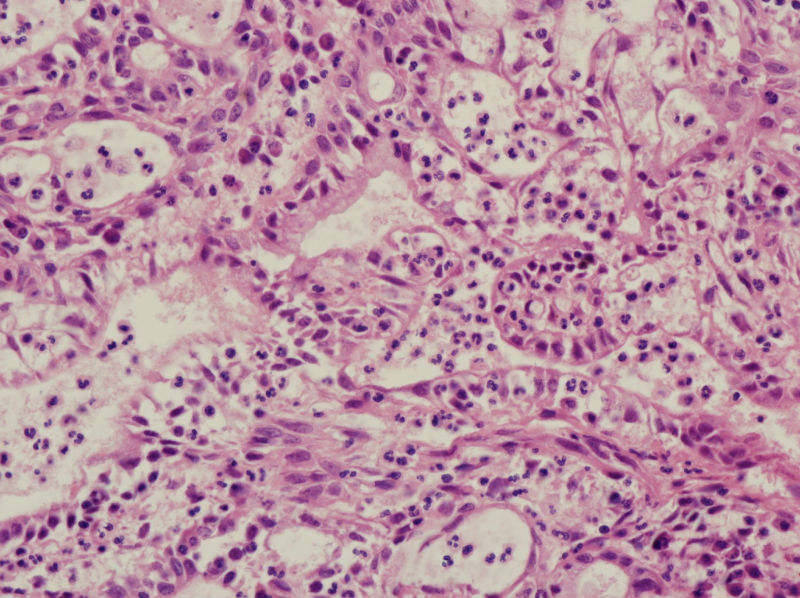

45岁,宫颈息肉?请老师指教

图1